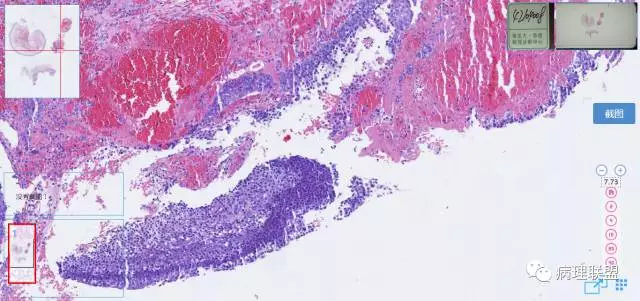

第二例

第一例和第二例病例我把典型图像压下来,是让我们以后注意,典型里找不典型,毛母质瘤主要由两种细胞构成,嗜碱细胞和影细胞构成,主要认识嗜碱细胞。